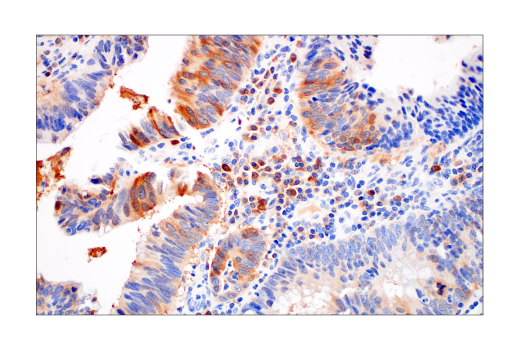

W, IHC-Bond, IHC-P, FC-FP

W: Western Blotting IHC-Bond: IHC Leica Bond IHC-P: Immunohistochemistry (Paraffin) FC-FP: Flow Cytometry (Fixed/Permeabilized)